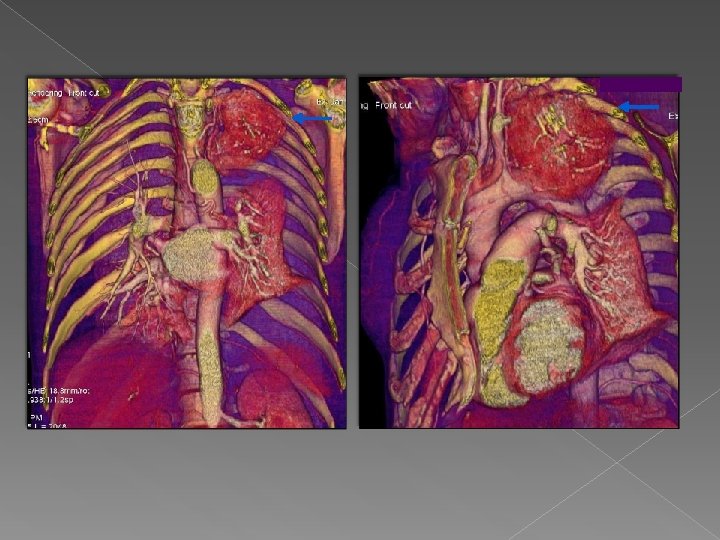

Caso 3 Mujer de 39 años con una tumoración extrapulmonar de gran tamaño, hipervascular

Caso 3 Mujer de 39 años con una tumoración extrapulmonar de gran tamaño, hipervascular con calcificaciones en su interior en vértice de hemitorax izquierdo diagnosticado de Tumor Castleman tras anatomía patológica. Valor del VR: nos aporta valiosa información sobre la morfología que adopta sobre todo de cara a la intervención quirúrgica.